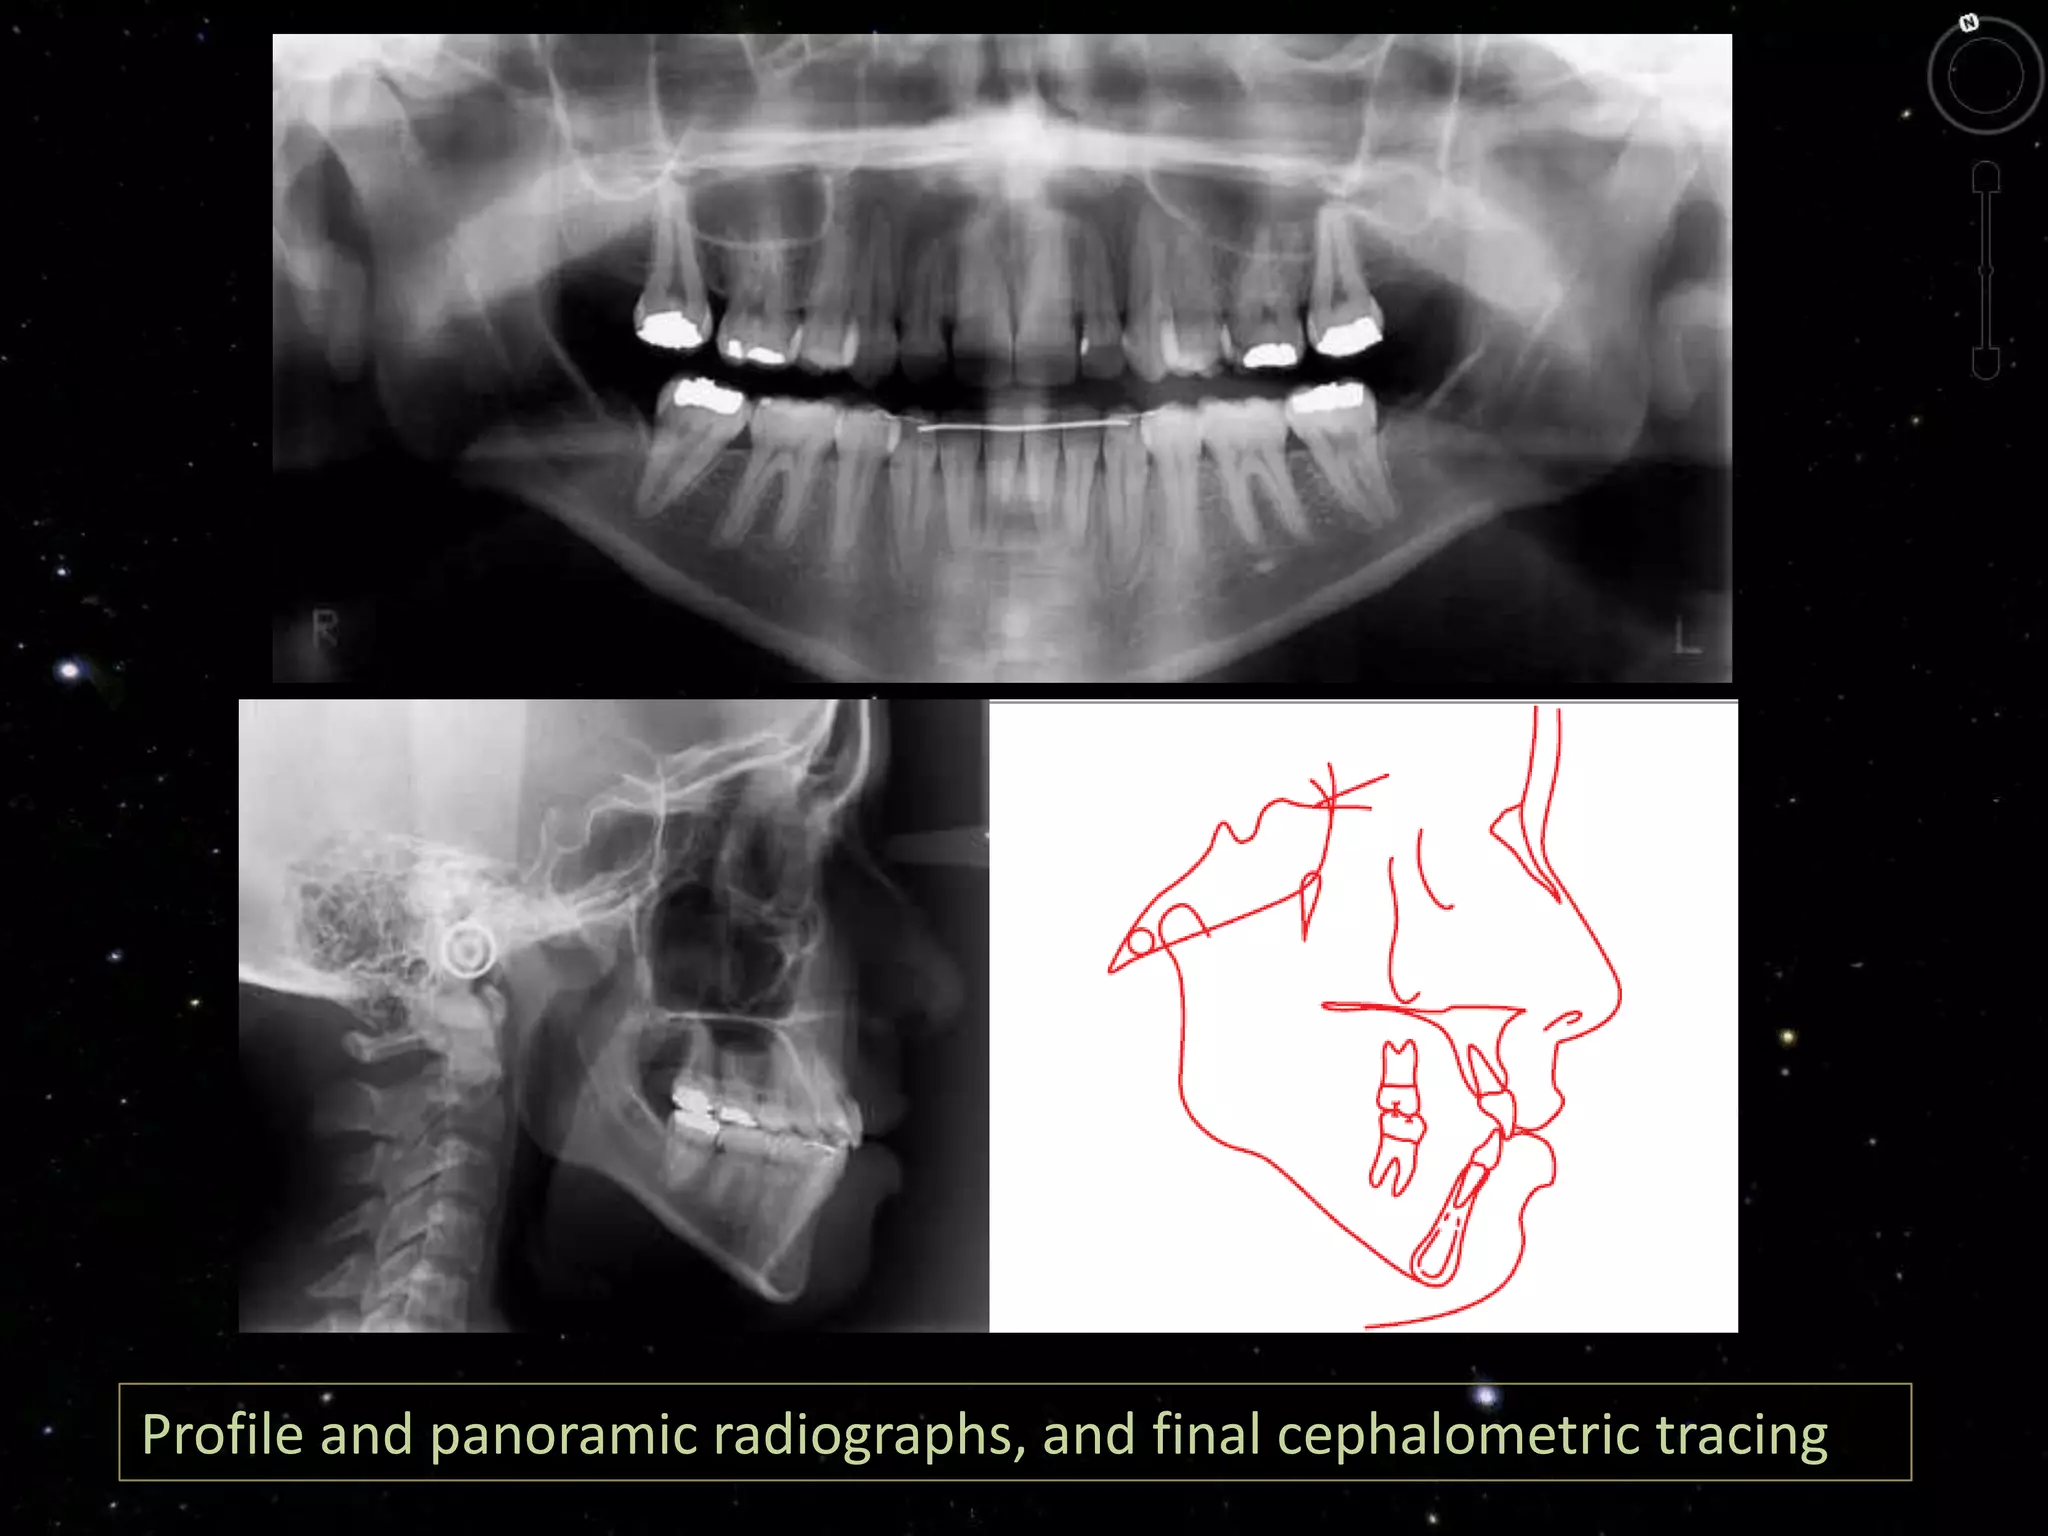

Finished treatment showing the treatment objectives were achieved

Profile and panoramic radiographs, and final cephalometric tracing

Finished treatment showingthe treatment objectives were achieved according to plan.

Profile and panoramicradiographs, and final cephalometric tracing